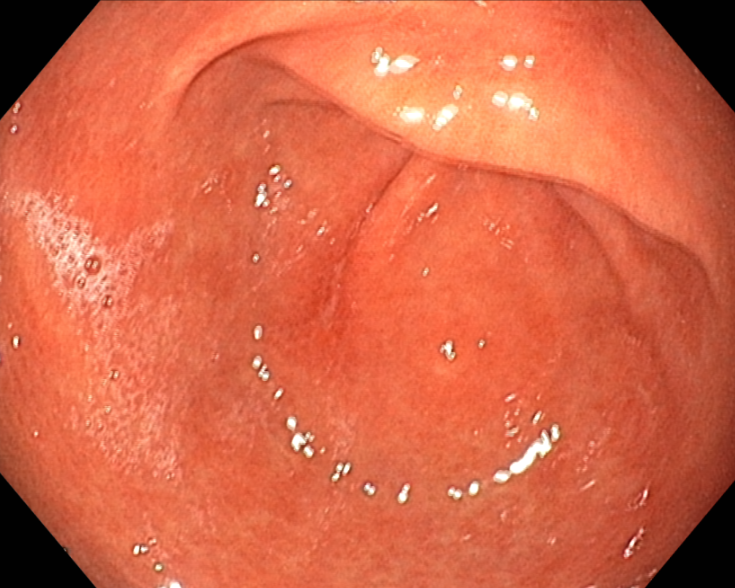

치료 8일 후 추적 위내시경을 시행하였습니다. 모두 호전된 소견.